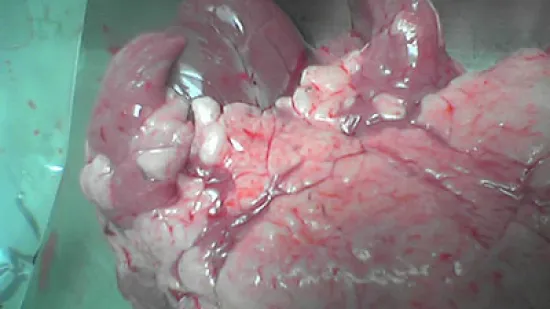

Augmentation des sevrés en retard avec respiration difficile et mauvaise réponse aux antimicrobiens. La mortalité passe de 4 à 30%. Quelle est la cause la plus probable de cette lésion ?